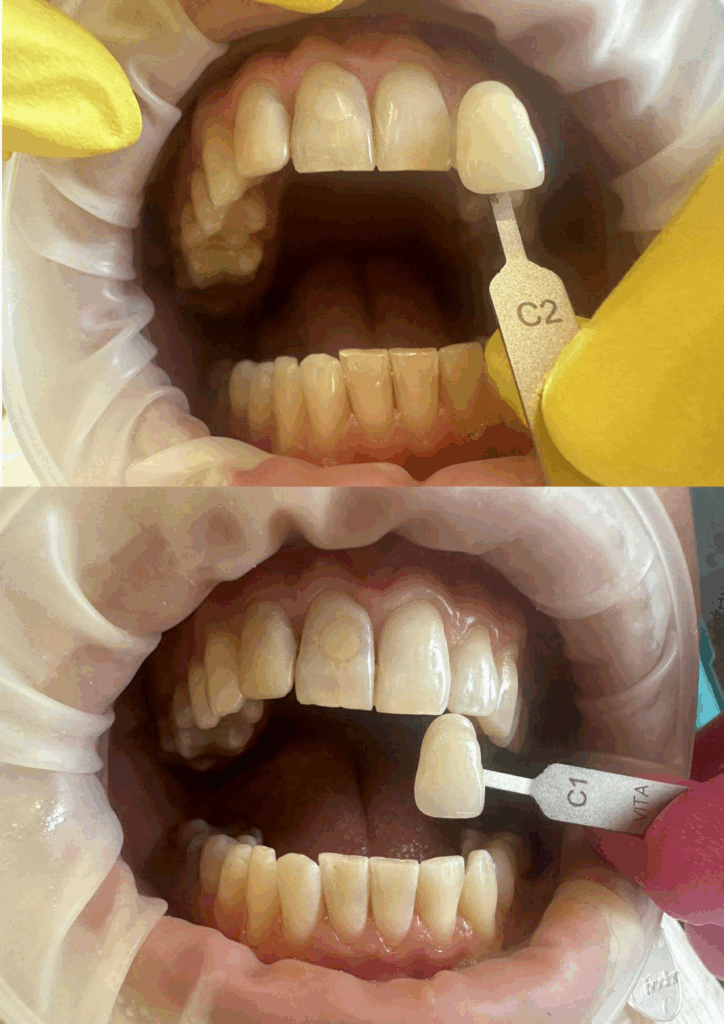

Higienizacja jamy ustnej – przed i po zabiegu

Usuwanie kamienia nazębnego i osadów

Efekt po skalingu